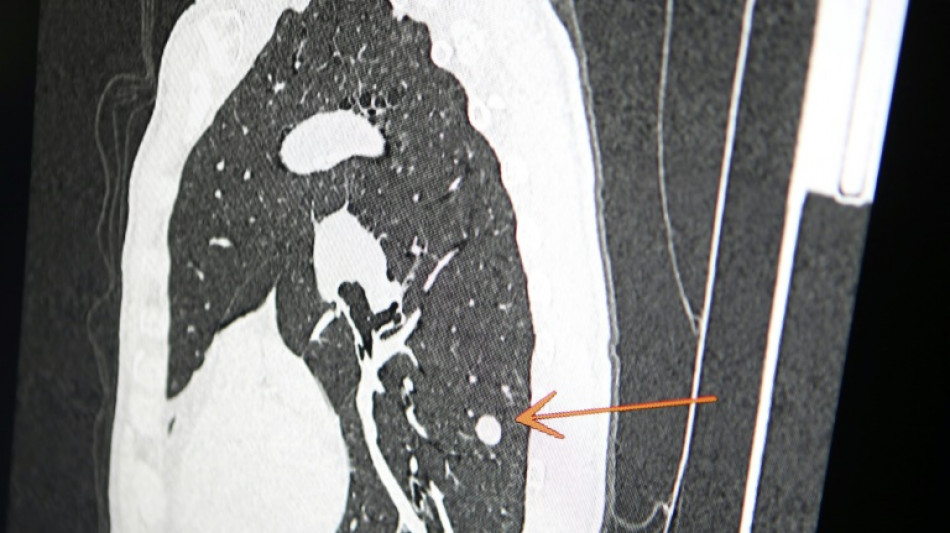

Una clínica del norte de Inglaterra dio un gran susto a cientos de pacientes al enviar el mensaje "diagnóstico: cáncer de pulmón agresivo con metástasis" en lugar de sus buenos deseos de Navidad, informó el diario The Sun el jueves.

El 23 de diciembre a las 15H49, los pacientes de este centro de salud de Askern, cerca de la ciudad de Doncaster, recibieron un mensaje de texto en su teléfono informándoles de este diagnóstico, pidiéndoles que rellenaran los formularios correspondientes y concluyendo: "Gracias".